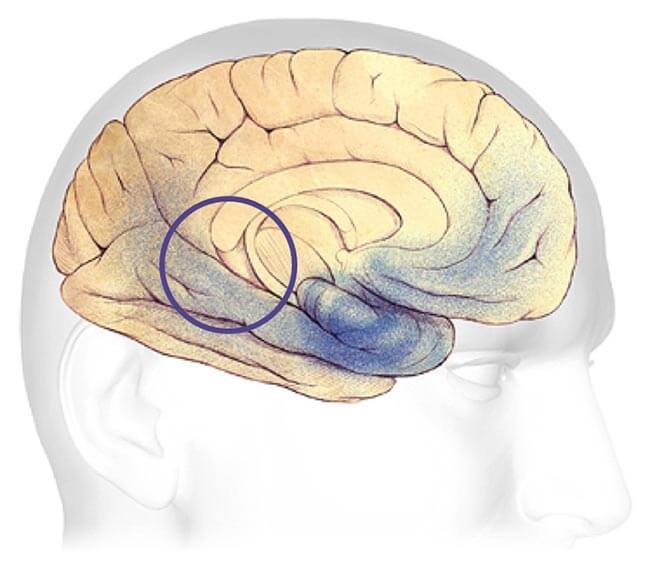

Progression Through the Brain

Plaques and tangles (shown in the blue-shaded areas) tend to spread through the cortex in a predictable pattern as Alzheimer's disease progresses. The rate of progression varies greatly. On average, a person with Alzheimer's lives four to eight years after diagnosis, but can live as long as 20 years, depending on other factors. The course of the disease depends in part on age at diagnosis and whether a person has other health conditions.

Severe Alzheimer's - may last from 1 - 5 years.

Severe Alzheimer's Disease

In advanced Alzheimer's disease, most of the cortex is seriously damaged. The brain shrinks dramatically due to widespread cell death. Individuals lose their ability to communicate, to recognize family and loved ones and to care for themselves.